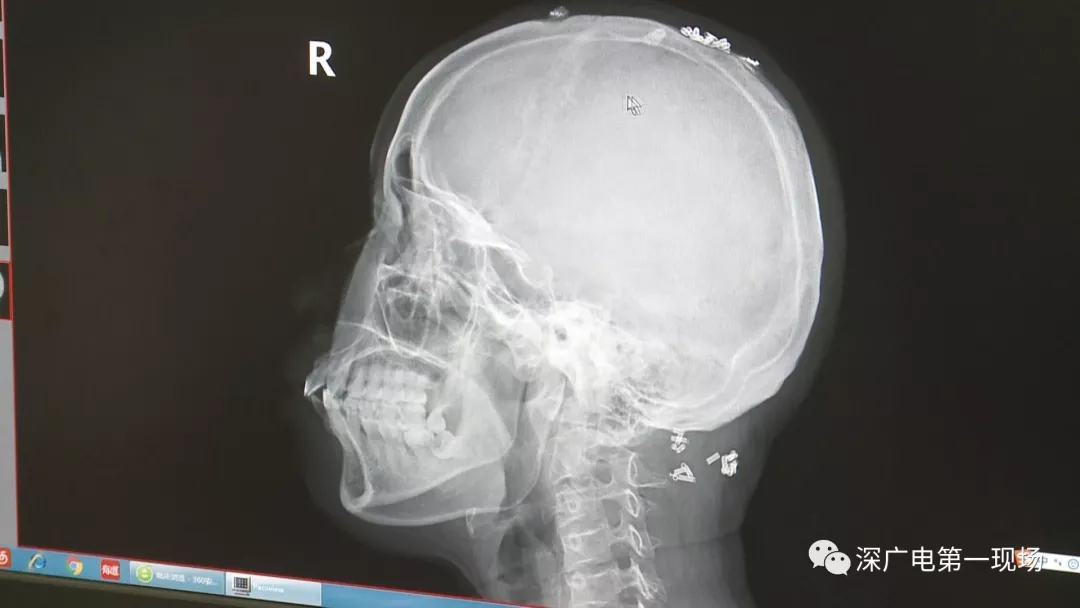

從X光影像圖片中可以看到

患者周身布滿(mǎn)了彈簧圈

深圳大學(xué)總醫(yī)院神經(jīng)外科副主任醫(yī)師陳富勇介紹,當(dāng)時(shí)檢查的時(shí)候發(fā)現(xiàn),該患者從頭部到腿部,基本上每個(gè)地方都有彈簧,很難數(shù)清具體數(shù)目。

陶主任表示,將這些彈簧圈取出也是一項(xiàng)大的工程,因?yàn)橛械亩家呀?jīng)形成了包塊,所以想要取出還得先定位,再挨個(gè)手術(shù)取出,目前醫(yī)院方面已經(jīng)將患者頭部和頸部的部分取出。